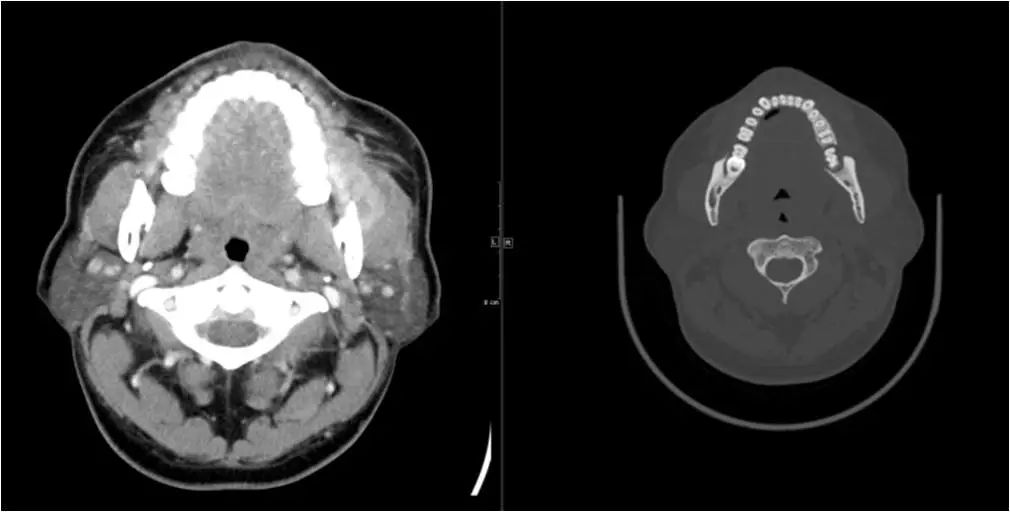

05 颌下间隙、颏下间隙

女,68岁,10天前自觉右侧下颌后牙区间断性钝痛,6天前发现右侧颌下区及颏下区肿胀,伴明显触压痛。

龋齿并冠周炎,咽旁间隙有肿大淋巴结。